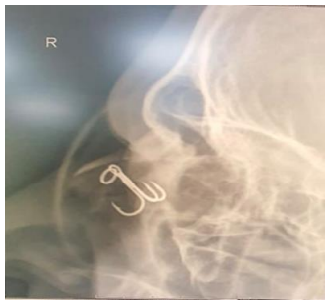

Fig 2: Lateral X-RAY

Visual acuity pre-operative was finger counting (Snellen).Pre op Xray of the orbit was done. Under general anaesthesia, the hook was rotated so that the intraocular barb emerged through the entry wound. The hook was gently pushed back and not pulled to avoid the barb to cause any undue traction on the surrounding ocular tissue. A small linear scleral wound was noticed, which was then repaired by 7-0 vicryl. The pars plana site of entry was subjected to cryotherapy to prevent any future vitreous traction and retinal detachment